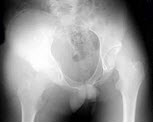

108、单项选择题

男,根据其正常骨盆影像图像,判断其最可能的年龄()

A.2岁左右

B.8岁左右

C.6岁左右

D.12岁左右

E.10岁左右

点击查看答案